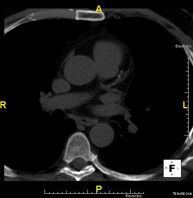

- Tórax- TC Tórax Prueba diagnóstica que consiste en obtener imágenes del tórax de alta definición anatómica (pulmones, corazón, mediastino, grandes vasos, caja torácica, etc.) mediante el empleo de un equipo de TC (Tomografía Computarizada). Dichas imágenes se estudian posteriormente en una estación de trabajo que permite reconstrucciones bidimendionales en diferentes planos del espacio y también reconstrucciones 3D (volumétricas). Algunos estudios requieren el empleo de contraste yodado para mejorar la definición de las imágenes. Prueba diagnóstica que consiste en obtener imágenes del tórax de alta definición anatómica (pulmones, corazón, mediastino, grandes vasos, caja torácica, etc.) mediante el empleo de un equipo de TC (Tomografía Computarizada). Dichas imágenes se estudian posteriormente en una estación de trabajo que permite reconstrucciones bidimendionales en diferentes planos del espacio y también reconstrucciones 3D (volumétricas). Algunos estudios requieren el empleo de contraste yodado para mejorar la definición de las imágenes.

- Angio-TC Aorta torácica Prueba diagnóstica que consiste en el estudio de la aorta torácica (principal arteria del tórax) mediante el empleo de un equipo de TC (Tomografía Computarizada). Esta técnica requiere el empleo de contraste yodado, y proporciona imágenes de alta definición anatómica. El uso del TCMD (TC Multidetector) acorta el tiempo de exploración, disminuye la dosis de radiación y mejora la calidad de la imagen. Gracias a los múltiples detectores, en determinados estudios se puede acoplar la obtención de la imagen con el latido cardíaco, técnica que permite el estudio de la válvula aórtica y de la raíz de la arteria aorta (primeros centímetros), donde el latido del corazón suele provocar múltiples artefactos de movimiento. Prueba diagnóstica que consiste en el estudio de la aorta torácica (principal arteria del tórax) mediante el empleo de un equipo de TC (Tomografía Computarizada). Esta técnica requiere el empleo de contraste yodado, y proporciona imágenes de alta definición anatómica. El uso del TCMD (TC Multidetector) acorta el tiempo de exploración, disminuye la dosis de radiación y mejora la calidad de la imagen. Gracias a los múltiples detectores, en determinados estudios se puede acoplar la obtención de la imagen con el latido cardíaco, técnica que permite el estudio de la válvula aórtica y de la raíz de la arteria aorta (primeros centímetros), donde el latido del corazón suele provocar múltiples artefactos de movimiento.

- Angio-TC Arterias pulmonares (Estudio TEP, Tromboembolismo Pulmonar) Prueba diagnóstica que consiste en el estudio de las arterias pulmonares mediante el empleo de un equipo de TC (Tomografía Computarizada) obteniendo imágenes bi y tridimensionales. En este estudio es imprescindible el uso de contraste yodado, el cual permitirá una mejor definición anatómica. Esta prueba está principalmente indicada en los casos de sospecha de tromboembolismo pulmonar (TEP) para descartar o confirmar la presencia de coágulos sanguíneos en el interior de las arterias. Prueba diagnóstica que consiste en el estudio de las arterias pulmonares mediante el empleo de un equipo de TC (Tomografía Computarizada) obteniendo imágenes bi y tridimensionales. En este estudio es imprescindible el uso de contraste yodado, el cual permitirá una mejor definición anatómica. Esta prueba está principalmente indicada en los casos de sospecha de tromboembolismo pulmonar (TEP) para descartar o confirmar la presencia de coágulos sanguíneos en el interior de las arterias.